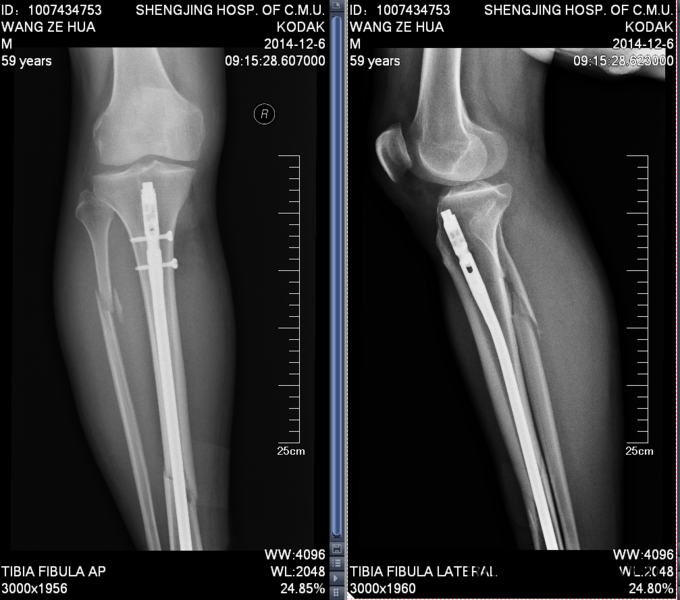

患者入院后消肿,冷敷等对症治疗,完善相关生化检查后,一星期后局部皮肤褶皱试验阳性后,行右胫腓骨骨折闭合复位髓内针内固定术。术后局部冷了消肿等治疗。